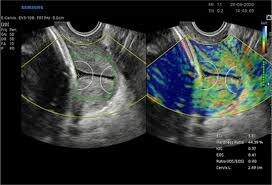

شفاآنلاین »سلامت» این بررسی که بوسیله پژوهشگران دانشگاه علوم پزشکی تهران با همکاری پژوهشگران داخلی و بینالمللی انجام شده است، نشان میدهد این روش جدید سونوگرافی به نام «الاستوگرافی» یا «ارتجاعنگاری» حساسیت و اختصاصیت چشمگیری دارد و جایگزینی امیدوارکننده برای روشهای معمول تشخیص سرطان دهانه رحم مانند کولپوسکوپی (مشاهده مستقیم دهانه رحم بوسیله یک عدسی بزرگکننده به نام کولپوسکوپ) است.

به گزارش شفاآنلاین سرطان دهانه رحم همچنان یک چالش بزرگ سلامت جهانی است و سالانه جان صدها هزار نفر را میگیرد، به ویژه در کشورهای با درآمد کم و متوسط که دسترسی به شیوههای غربالگری محدود است. روشهای تشخیصی مرسوم مانند کولپوسکوپی اغلب به مهارت پزشک متکی هستند و ممکن است نتوانند علائم اولیه را شناسایی کنند، اما الاستوگرافی - که در آن سفتی بافت برای تمایز بین ضایعات خوشخیم و بدخیم اندازهگیری میشود - میتواند این وضعیت را تغییر دهد.

الاستوگرافی خواص الاستیک و سفتی بافت نرم را نقشهبرداری میکند و اساس آن بر این است که سخت یا نرم بودن بافت، اطلاعات تشخیصی در مورد وجود یا وضعیت بیماری در آن بافت به دست میدهد. به عنوان مثال، تومورهای سرطانی اغلب سختتر از بافت اطراف خود هستند و کبدهای بیمار سفتتر از کبدهای سالم هستند.

بررسی پژوهشگران مرکز تحقیقات رادیولوژی نوین و تهاجمی دانشگاه علوم پزشکی تهران نشان میدهد این فناوری دارای حساسیت و اختصاصیت بالا (به ترتیب ۸۸.۳ درصد و ۹۲ درصد) برای تشخیص سرطان دهانه رحم است که نشاندهنده عملکرد تشخیصی کلی عالی است.